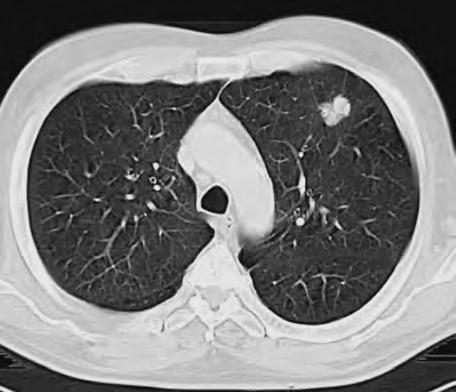

Diferenciální diagnóza

Expanzivní ložisko vCNS může být někdy způsobeno benigním patologickým procesem (abscesem, kavernomem, meningeomem), ale může jít také ometastázu známého nebo doposud ukrytého tumoru, viz obr. 1.4 a1.5. Do mozku často metastazují následující tumory: bronchogenní karcinom, obzvláště jeho malobuněčná varianta, karcinomy prsu aledvin. V80 %případů jsou tyto metastázy uloženy supratentoriálně.

Metastázy mohou vCNS vytvořit jak solitární, tak ivícečetná ložiska, mohou však také infiltrovat meningy (bronchogenní karcinom, karcinomy prsu ižaludku).